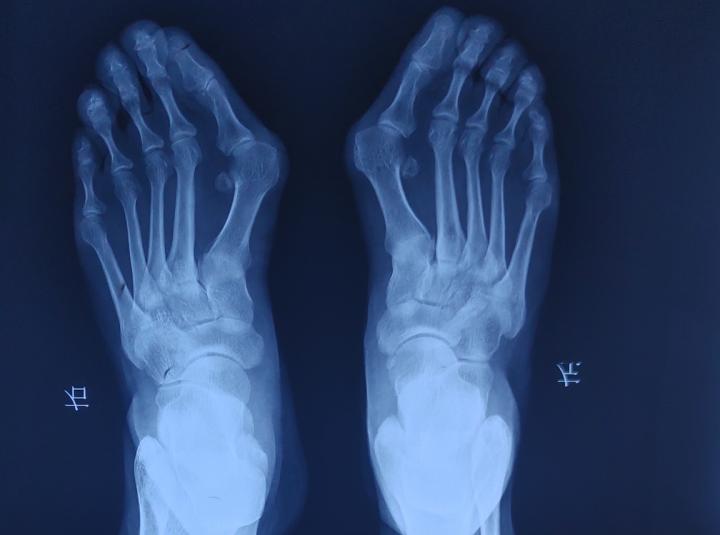

拇外翻X光:第一跖骨向内侧偏斜,第一趾骨向外侧偏斜,两者形成犄角

痛风X光,侵蚀第一跖趾关节及骨头

除外上述症状 ,还有一些实验室等检查,能够有效诊断拇外翻和痛风。X光能有效确诊拇外翻,通过X光能够清晰的看到拇外翻偏斜的角度,第一二跖骨间角度,关节间隙等;X光也能看到痛风石的堆积情况,痛风石会侵蚀骨头,出现在第一跖趾关节周围的痛风石堆积,对第一跖骨头的侵蚀情况也清晰可见。